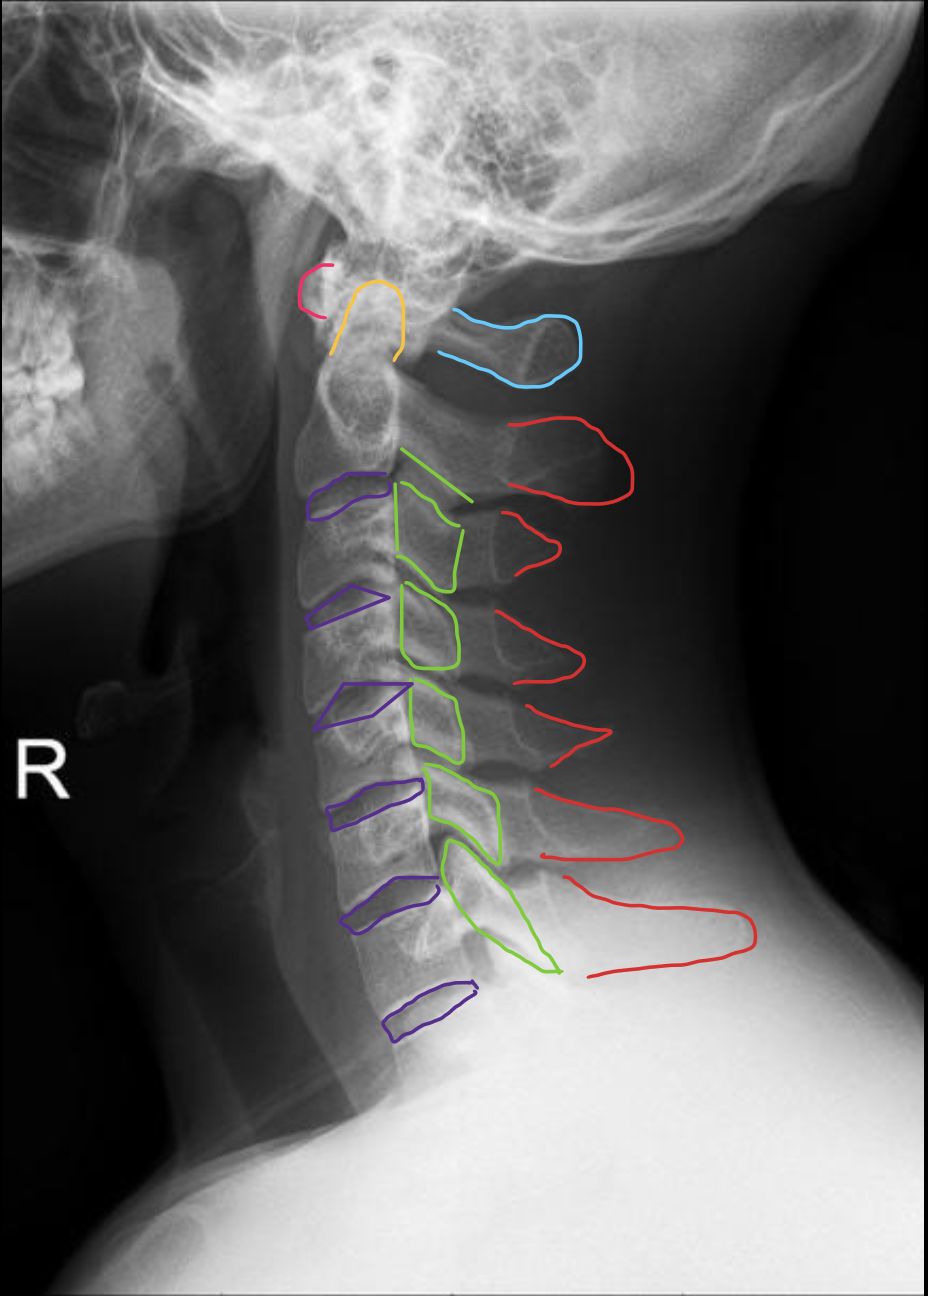

C1

C2

C3

C4

C5

C6

C7

T1

1st rib

寰椎前结节

C1 anterior tubercle

寰椎后弓及后结节

C1 posterior arch & tubercle

关节突

Articular process

椎间孔

Intervertebral Foramina

椎弓根

Pedicle

椎间盘

Intervertebral disc

关节突关节(小关节)

Zygapophyseal

齿状突(枢椎齿突)

Odontoid

Posterior arch & Tubercle of C1

棘突

Spinous process

椎间盘(Intervertebral Disc)

IVD